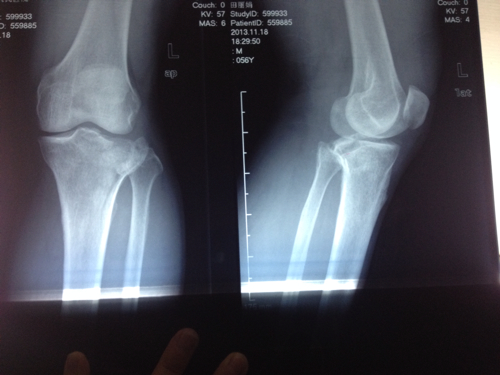

因此,在2岁前不应贸然诊断为本病。 X线表现 受累侧小腿向内弯曲,呈膝内翻畸形,胫骨内髁增大,其上方关节面向内、下、后方倾斜。邻近骨骺的干骺端内侧部分也向内侧扩展,且可出现斑点状密度不均匀或不规则钙化,胫骨干内侧皮质增厚。膝关节造影示胫骨关节面逐渐由水平发展至塌陷,内侧半月板代偿性异常增厚,以维持关节的稳定。

胫骨内髁骨软骨病的辅助检查方法主要是X线检查,X线表现为:受累侧小腿向内弯曲,呈膝内翻畸形,胫骨内髁增大,其上方关节面向内、下、后方倾斜。邻近骨骺的干骺端内侧部分也向内侧扩展,且可出现斑点状密度不均匀或不规则钙化,胫骨干内侧皮质增厚。膝关节造影示胫骨关节面逐渐由水平发展至塌陷,内侧半月板代偿性异常增厚,以维持关节的稳定。

临床诊断主要是通过X线检查,表现为:受累侧小腿向内弯曲,呈膝内翻畸形,胫骨内髁增大,其上方关节面向内、下、后方倾斜。邻近骨骺的干骺端内侧部分也向内侧扩展,且可出现斑点状密度不均匀或不规则钙化,胫骨干内侧皮质增厚。膝关节造影示胫骨关节面逐渐由水平发展至塌陷,内侧半月板代偿性异常增厚,以维持关节的稳定。